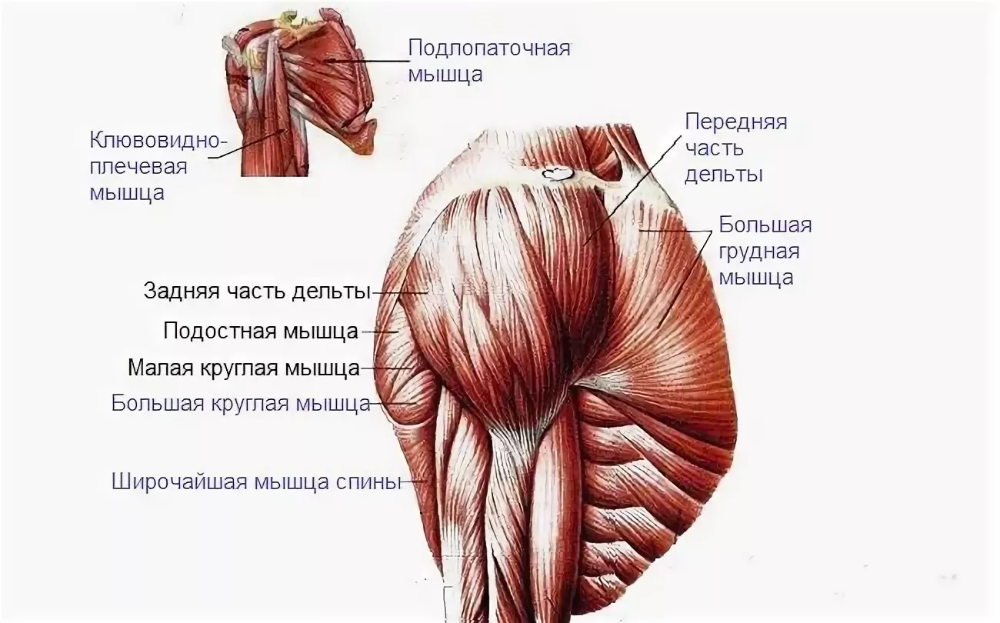

Фотографии поддельтовидной мышцы плечевого сустава